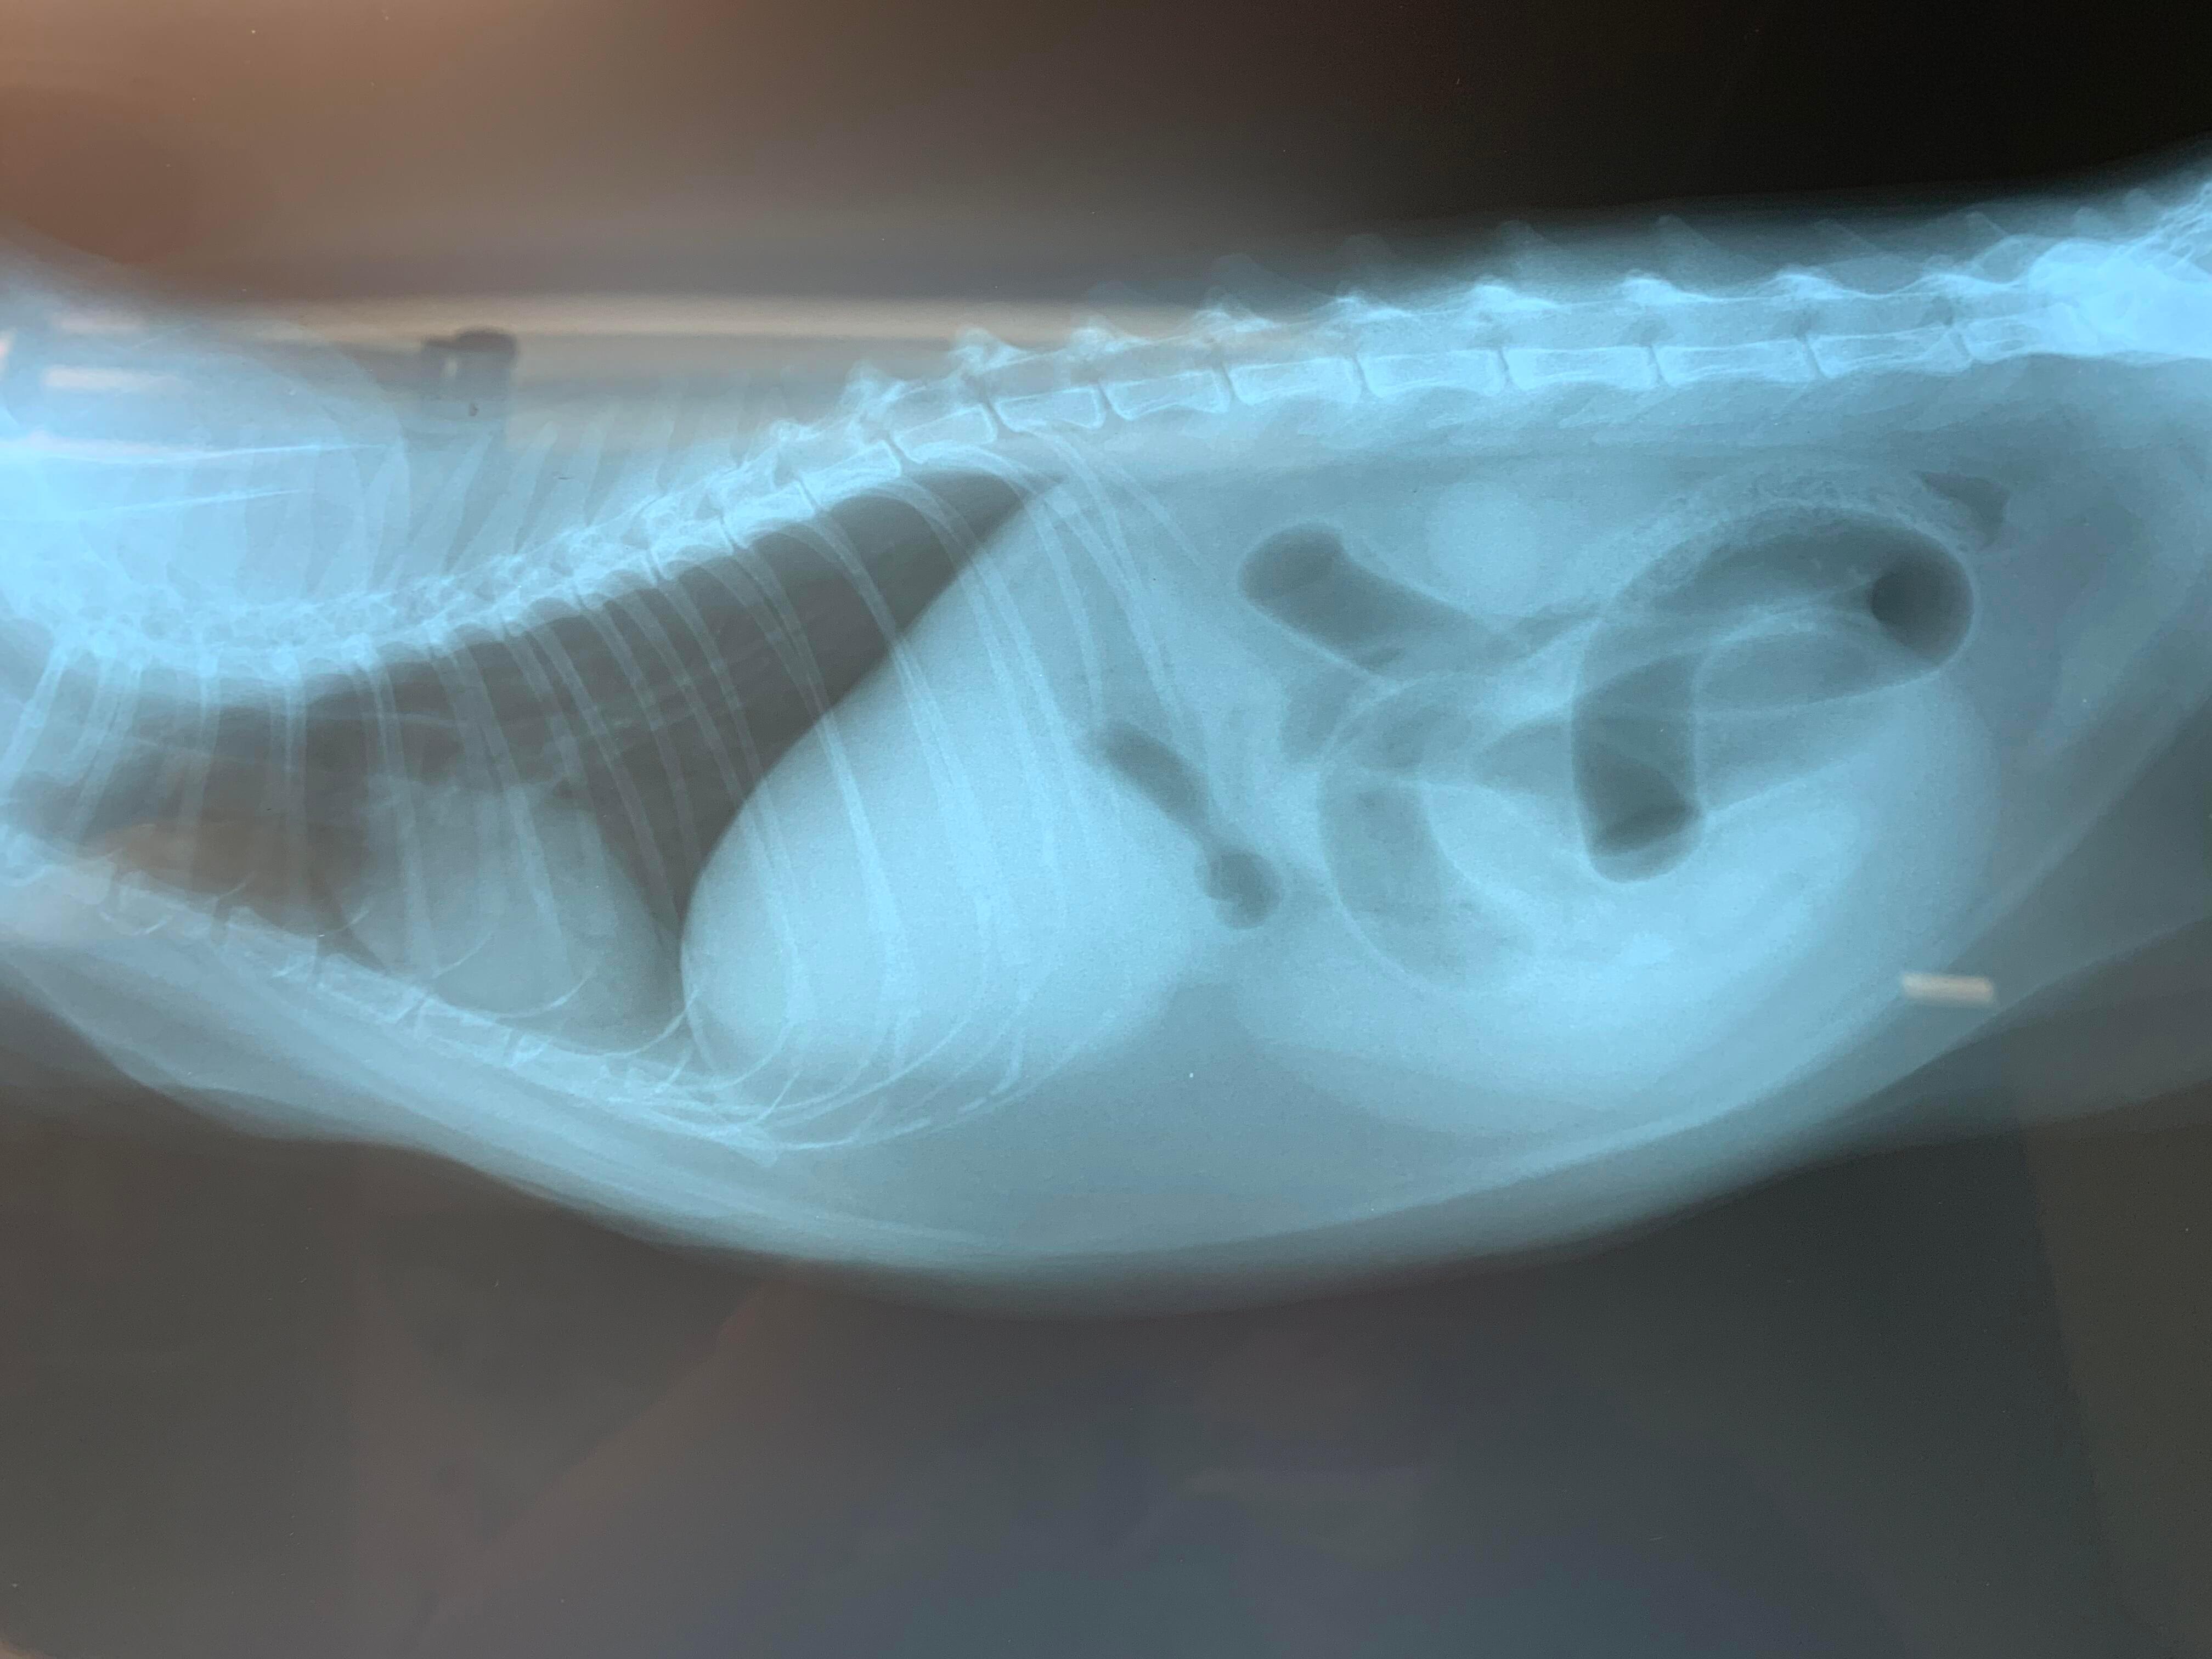

Could I get a second opinion on my cat's x-ray? She is 15 years old and healthy and robust and active, but suddenly seems unwell, not eating so good, some stomach upset. I'd like to know if the vet sees some illness in the x-ray.

Hello and thank you for contacting Petco Pet Education Center, formerly Petcoach. It is difficult to make the diagnosis from the picture you posted but the rounded, egg-shaped area in the central part of the abdomen looks abnormal. Also, a part of the kidney is surprisingly dense, which could be a sign of a disease. I would not be able to make a diagnosis without having Coco fully examined and receiving full clinical history. However, I am concerned about the large shadow in the abdomen and the dense part of the kidney. The chest looks normal for a cat of her age. If you have more x-rays of Coco (ideally a view called dorso-ventral) that would be very helpful if post them on Petco Pet Education Center, formerly Petcoach.